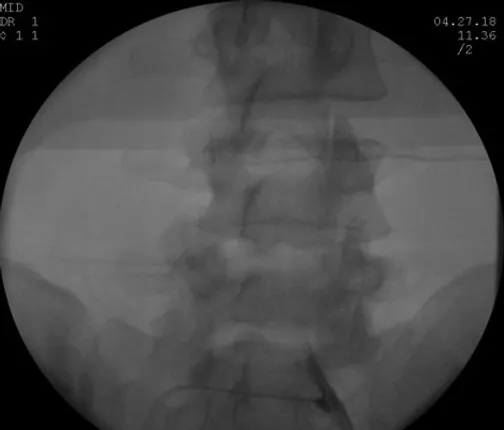

Decided to proceed with Right sided L5 and S1 Transforaminal Epidural Steroid Injections

- 1st on 09/15/2017 > 70% relief of symptom

- 2nd on 10/20/2017 > 80% relief of symptom

- 3rd on 11/21/2017 > 90% relief of symptom

First Lumbar Bilateral L5-S1 Transforaminal Epidural Steroid Injection 11/01/2016 > 30% Relief

Second Lumbar Bilateral L5-S1 Transforaminal Epidural Steroid Injection 11/29/2016 > 50% Relief

Third Lumbar Bilateral L5-S1 Transforaminal Epidural Steroid Injection 12/27/2016 > 70% Relie